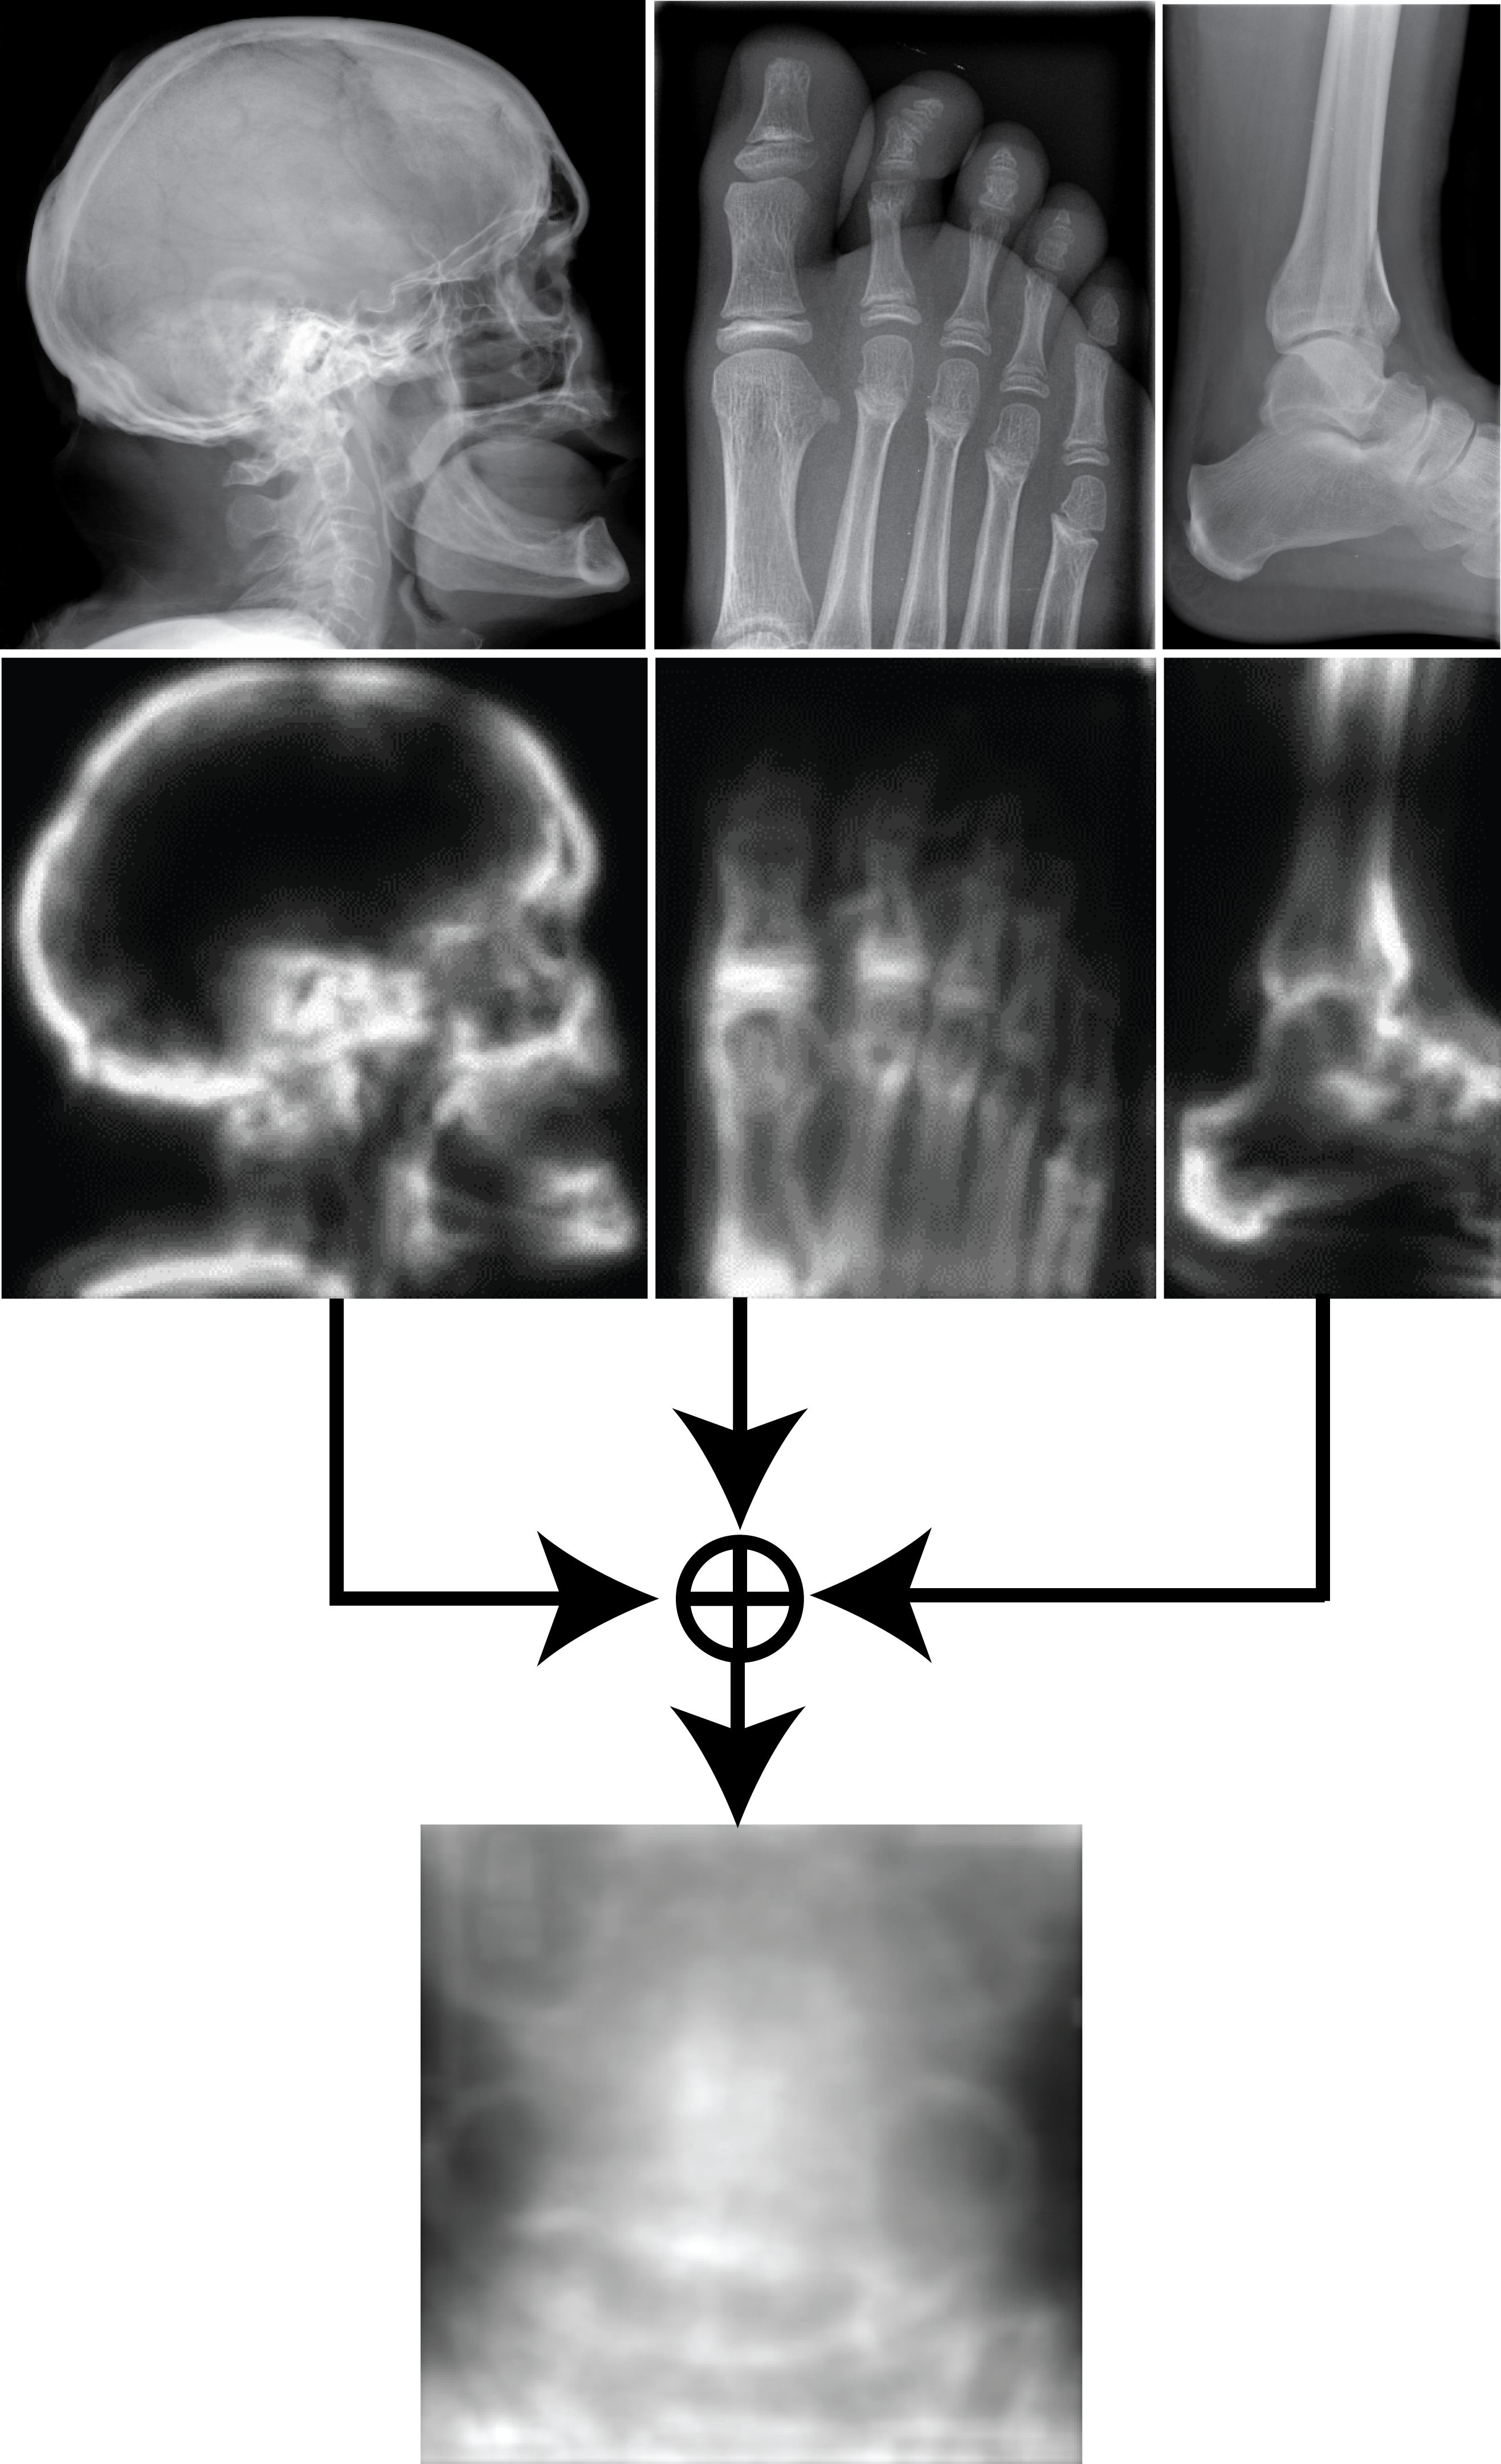

Saliency maps of all training images are generated and averaged to calculate a saliency template (Algorithm 2). Figure 1 shows three images, their saliency maps, and the saliency template created by averaging all saliency maps. The average of saliency maps is first calculated internally within each class, then the average is taken across all classes.

The salient, less salient and not salient areas are defined for training data by dividing images to sub-blocks. Then, based on the saliency template, the folding is applied. The new images with reduced area can now be used for local pattern analysis.

Folding the rectangular region within image resulting in an image can be given through whereas the sign “” denotes the set-theoretical subtraction. The main purpose of folding is to reduce image area without loosing information but reducing the dimensionality of features (see Fig. 2). The folding steps are described in Algorithm 3.